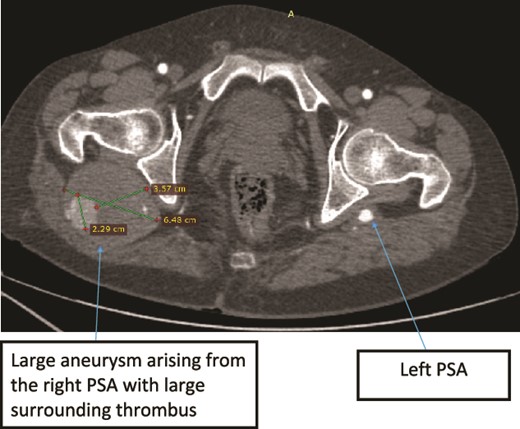

Case 2—axial images of LL CTA of the bilateral LL arteries at the level of the femoral head showing large bilateral PSAs and a large aneurysm with surrounding thrombus of the right PSA.